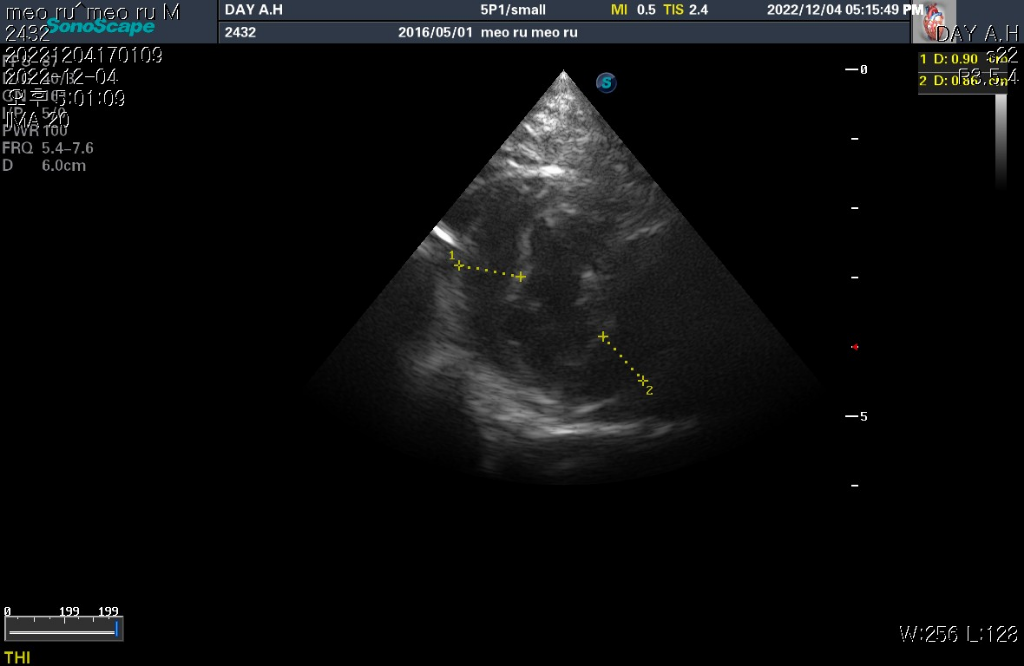

하지만 심장 질환의 잠정적 확진 golden standard는 심장 초음파 검사로 심장 초음파 검사상 심장의 벽 구조가 6mm이상이라면 HCM의 가능성이 매우 높다고 판단합니다.

현재 첨부한 사진상에서 6mm이상의 직경을 보이는 사진들이 존재하기 때문에 해당 검사를 진행한 수의사의 기준상 HCM의 가능성이 높다고 판단하는것은 합리적입니다.